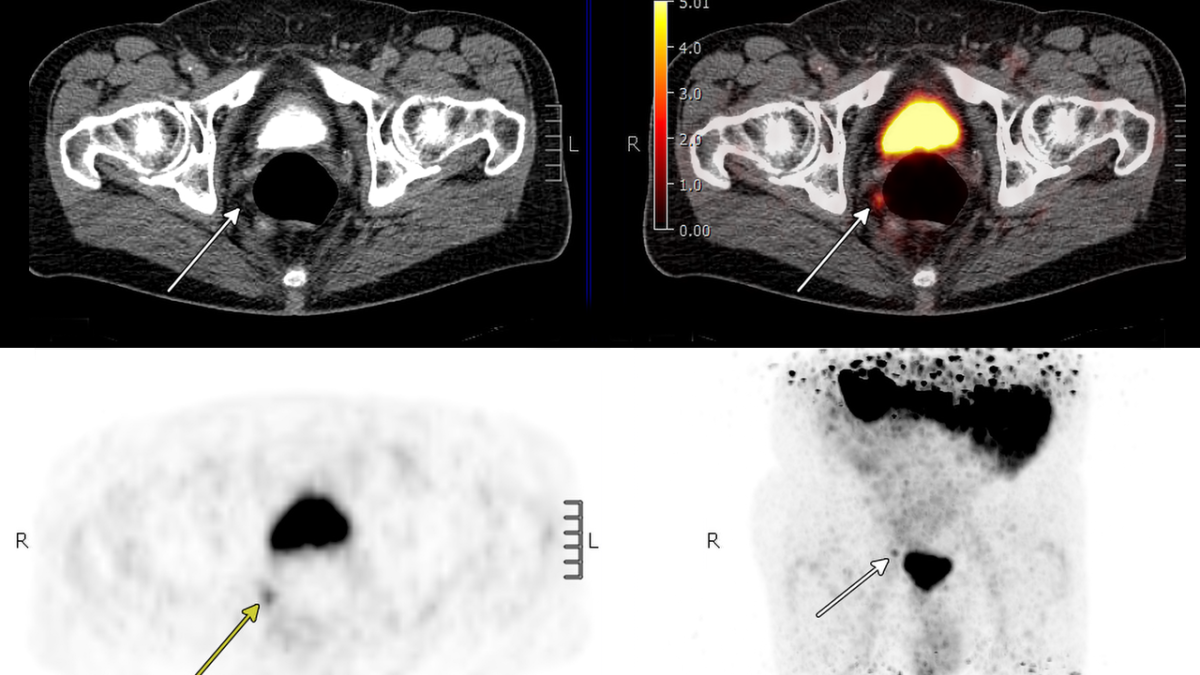

PSMA PET/CT utilizes a radioactive tracer that binds to prostate-specific membrane antigen (PSMA), a protein found on the surface of most prostate cancer cells. This allows clinicians to visualize even very small deposits of cancer that are invisible on conventional scans. Unlike traditional imaging, which primarily provides anatomical details, PSMA PET/CT offers functional imaging, revealing the biological activity of the cancer and improving the accuracy of staging. The scan can determine if the disease remains confined to the prostate bed, has spread to nearby lymph nodes, or has metastasized to other parts of the body.

The UCLA-led study followed 113 men whose PSA levels rose after prostate cancer surgery. All patients underwent PSMA PET/CT scans prior to receiving radiation therapy, and their outcomes were tracked for a median of five years. The scan results directly informed treatment decisions, including whether to treat the entire pelvis or just the prostate bed, whether to add androgen deprivation therapy (ADT), and the appropriate radiation dosage.

Researchers found that approximately 60% of patients had detectable cancer on the PSMA PET/CT scans, with many exhibiting spread beyond the prostate bed to lymph nodes or bones. This allowed for adjustments to treatment strategies that would not have been possible with traditional imaging.